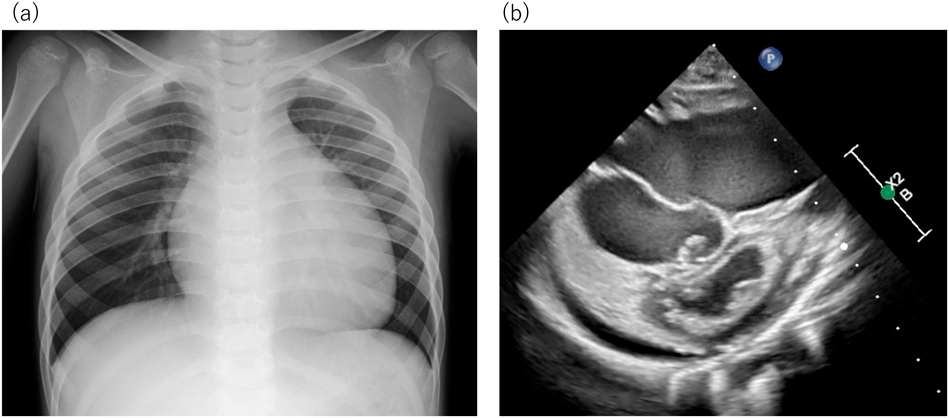

4歳男児,身長92 cm(−2SD),体重16 kg(+1SD).入院3カ月前から徐々に起床時の顔面浮腫が増強,易疲労感を訴えるようになり近医を受診した.胸部単純X線で心拡大を認め,心臓超音波検査で右心系の著明な拡大と重度の三尖弁逆流を認め,肺高血圧症の疑いとして当科に紹介入院となった.入院時,心音は整,2音の亢進,Levine3/6度の逆流性収縮期雑音を聴取し,下腿に圧痕性浮腫を認めた.体血圧106/59 mmHgに対し心臓超音波検査で三尖弁逆流圧較差(tricuspid regurgitation pressure gradient; TRPG)100 mmHgと重度の肺高血圧を認めた(Fig. 1).精査を進め,肺高血圧の原因となるような膠原病,感染症,先天性心疾患などの基礎疾患は認められず,家族歴がなく,遺伝子検査が未実施のため,臨床的にIPAHと診断した.心臓カテーテル検査によるAVTが必要と考えられたが,カテーテル検査時の鎮静による循環動態の悪化が懸念されたため,まず酸素吸入・肺血管拡張薬による治療を先行し,心臓カテーテル検査を行う方針とした.

Fig. 1 Examinations on admission

(a) Chest X-ray shows cardiomegaly, (b) Cardiac echo shows the dilated right ventricle and the compressed left ventricle.